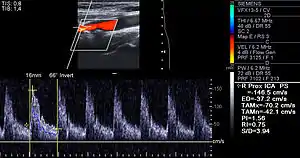

Doppler ultrasound of right internal Carotid artery with calcified and non-calcified plaques showing less than 70% stenosis

Lumen stenosis that is greater than 75% was considered the hallmark of clinically significant disease in the past because recurring episodes of angina and abnormalities in stress tests are only detectable at that particular severity of stenosis. However, clinical trials have shown that only about 14% of clinically debilitating events occur at sites with more than 75% stenosis. The majority of cardiovascular events that involve sudden rupture of the atheroma plaque do not display any evident narrowing of the lumen. Thus, greater attention has been focused on "vulnerable plaque" from the late 1990s onwards.[64]